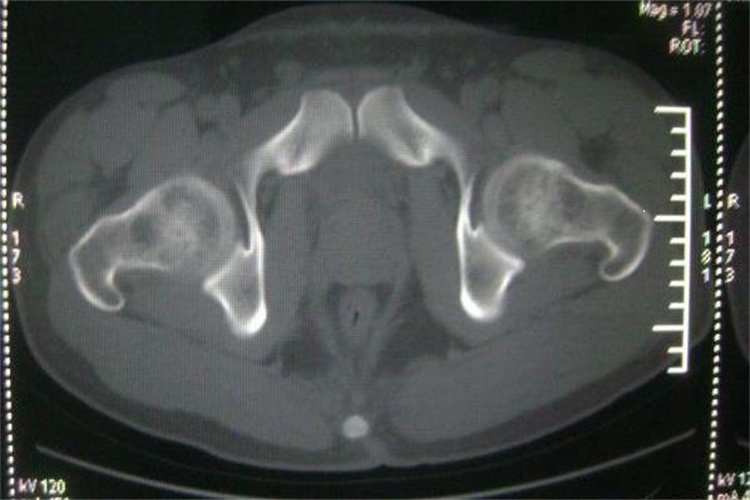

髋关节由髋臼和股骨头所构成,属于多轴的球窝关节,髋臼的周缘附有纤维软骨构成的髋臼唇。髋臼切迹被髋臼横韧带封闭,使半月形的髋臼关节面扩大为环形,以紧抱股骨头,髋臼窝内充填有脂肪组织。髋关节的关节囊坚韧致密,向上附着于髋臼周缘及横韧带,向下附着于股骨颈,前面达转子间线,后面包裹股骨颈的内侧2/3。